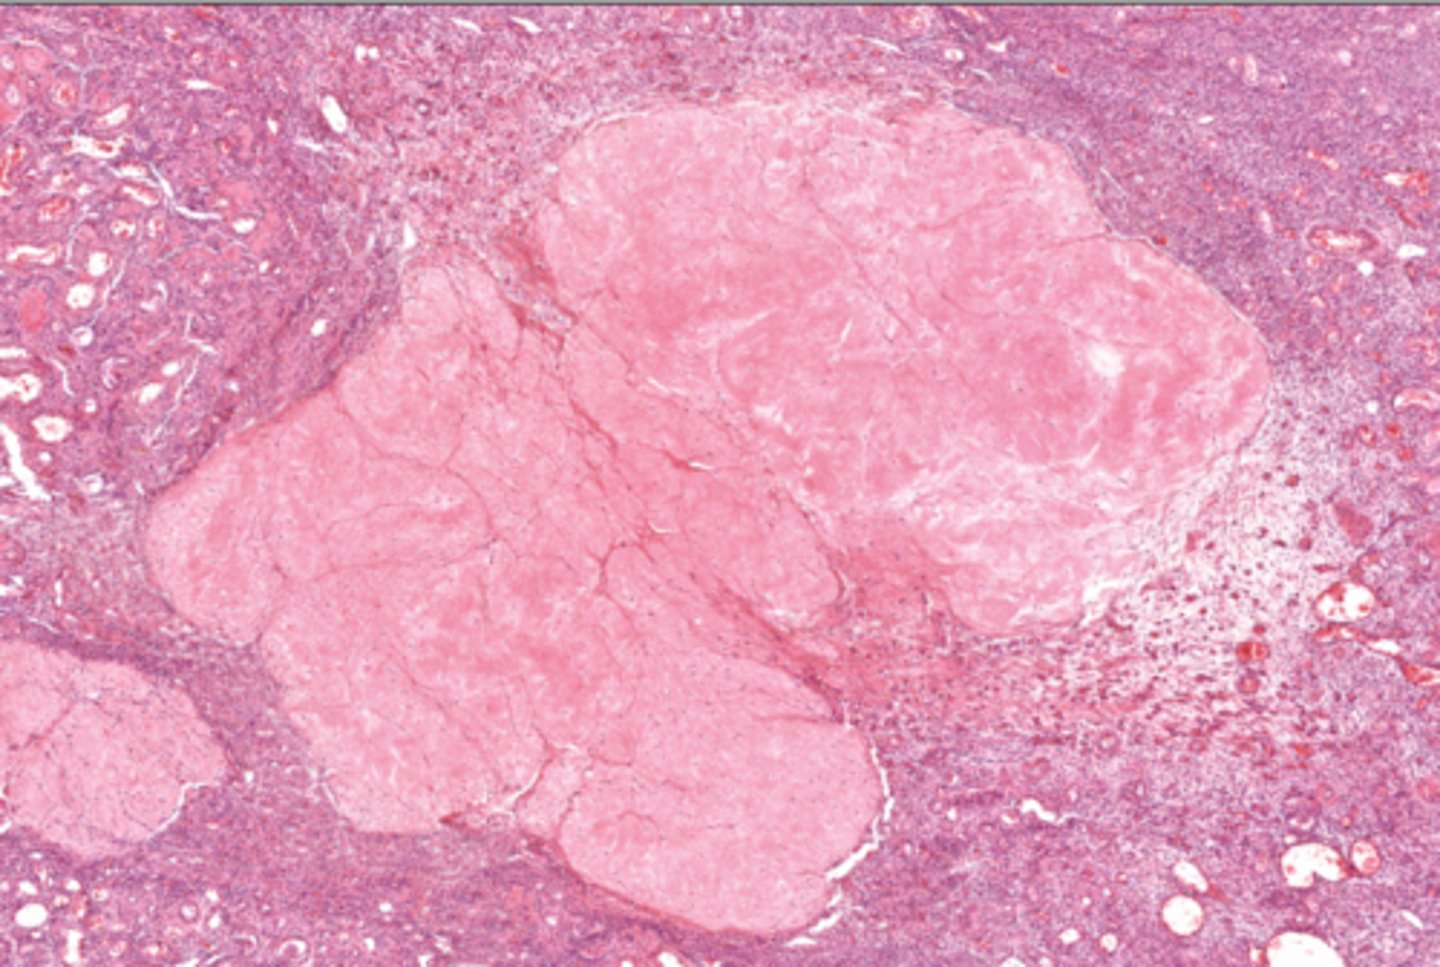

Tertiary follicle

4

Tertiary follicle

4

Mature follicle

5

Mature follicle

Mature follicle

7

Antrum

10

Zona pellucida

9

Theca folliculi

8

Corona radiata